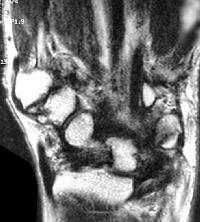

Sections through the carpal tunnel -  looking for a hook of hamate fracture or tendon discontinuity - were read as normal, although there may be a subtle signal irregularity through the hook of the hamate:

Is that a tendon rupture adjacent to the pisotriquetral joint?